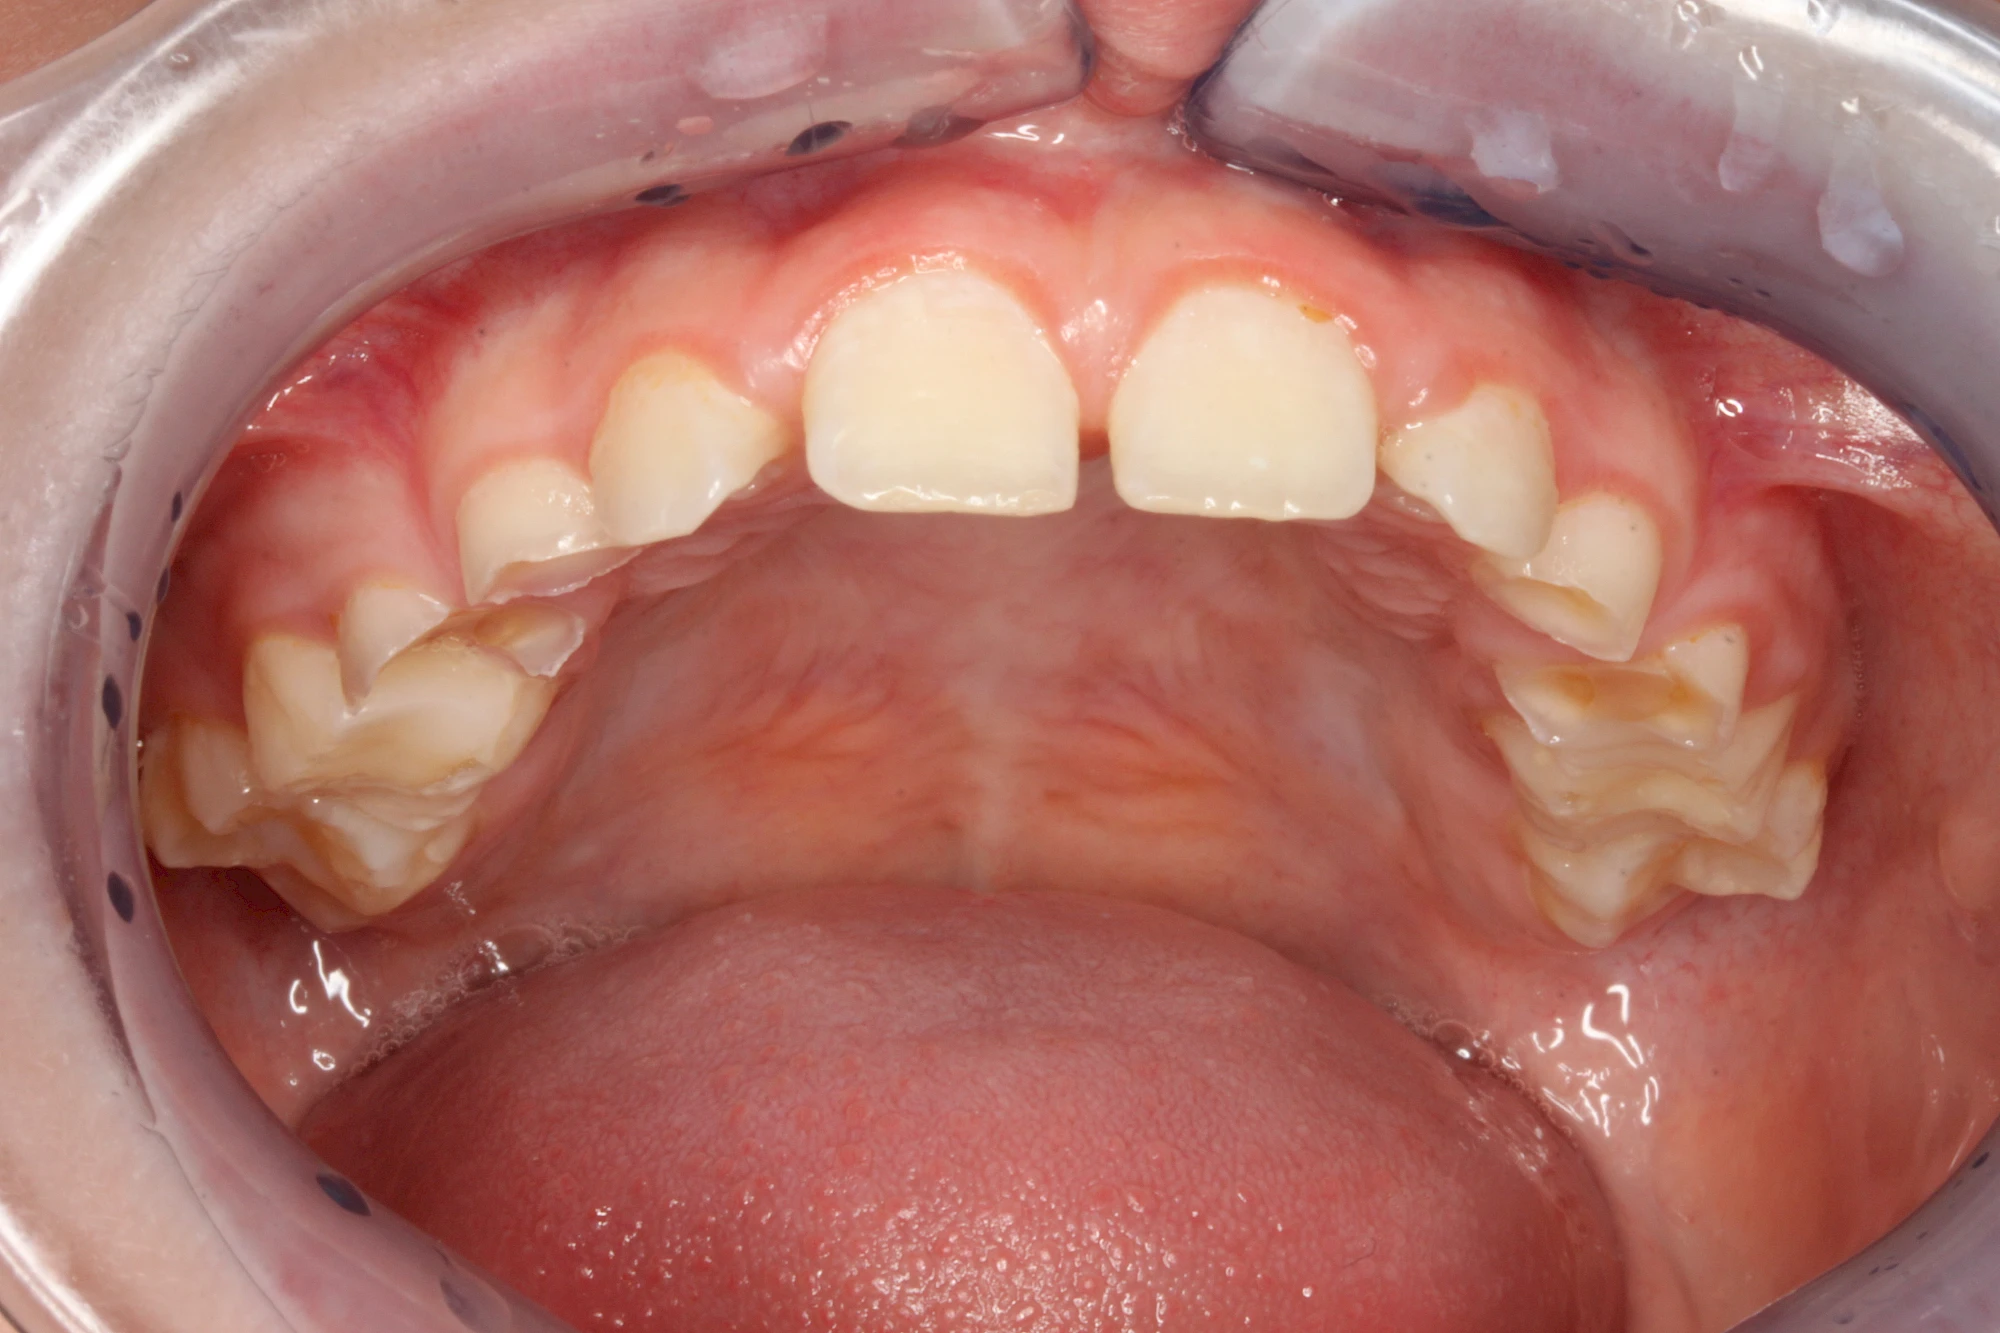

Auswaschung (Erosion) dagegen ist eine Verschleißerscheinung der Zähne aufgrund von immer wiederkehrenden Säureangriffen durch die Nahrung, verstärkt zum Beispiel durch den Genuss säurehaltiger Getränke oder Speisen. Auch bei Menschen mit einer Essstörung (z. B. Bulimie) können die Zähne durch die Magensäure ausgewaschen erscheinen.